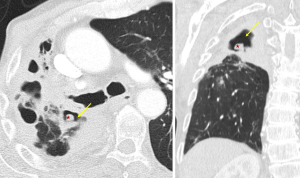

Imaging findings of septic emboli include multiple subpleural, wedge-shaped nodules, which progress into cavities within days (Figure 6) (16). Cavitation is observed in up to 47% of cases on chest X-ray and up to 85% on CT (8). The “feeding vessel” sign, which indicates a distinct vessel leading to the center of the pulmonary nodule, is suggestive of septic emboli (8). Pleural effusion, hilar lymphadenopathy, and mediastinal lymphadenopathy may also be seen (8). The rapid progression of nodules to cavities helps to differentiate them from malignancies (8).